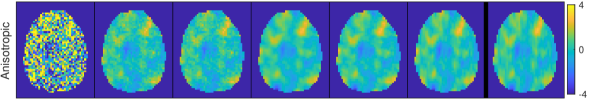

4.2.3 Prior simulation

To better understand the meaning of the different priors in practice, Fig. 4 displays samples from the spatial priors using the estimated hyperparameters for the first regressor of the different datasets. The M and ICAR priors produce fields that vary quite rapidly, while the second order priors give realizations that are more smooth. For the word object dataset we note that the short estimated range for M gives a sample with much faster variability than the sample from ICAR, which looks unrealistically smooth. This illustrates the problem with using the infinite range ICAR prior for a dataset where the inherent range is much shorter.